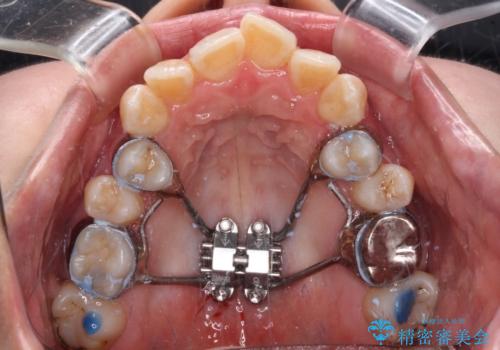

2. 【モニター】急速拡大装置 狭い歯列を拡大してワイヤー装置で短期間治療の治療中